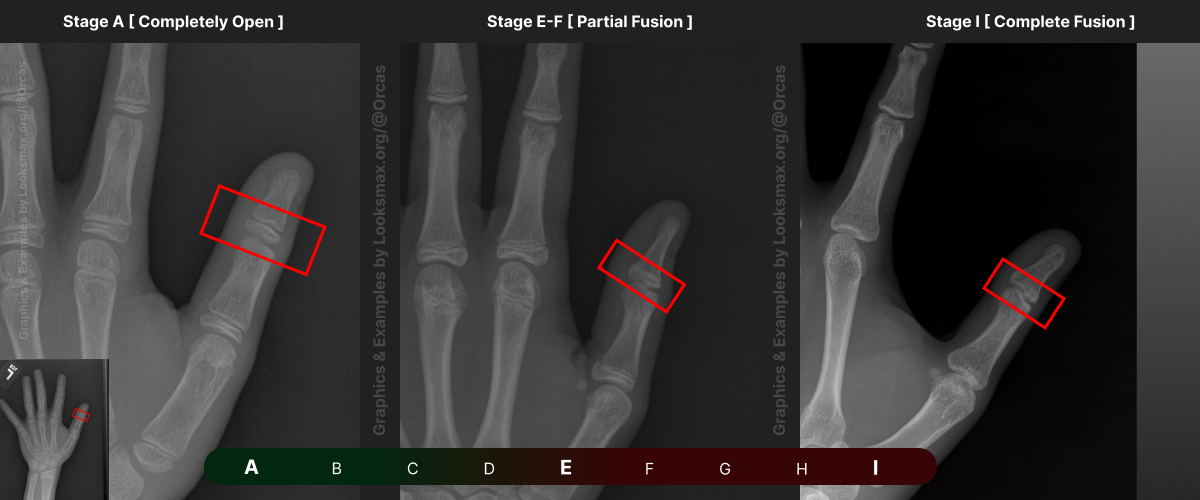

I added references for stages A (Completely unfused), E-F (Partial fusion, basically late stages of puberty), and I (Complete Fusion)

You will have to eyeball this now using your own xrays, I’ve given three examples and some wiggle-room for letters using a reference bar (green-red) below the image, write down your estimated guesses in a text file until you finish all 13 bones.

Don’t doubt yourself, eyeballing isn’t perfect but it still works well, just choose & continue.

Ex.

“My Radius looks more fused than the image from E-F, but its not as fused as I, it’s closer to the 2nd picture though, so I’ll rate it G” And continue

Bonetype: 1st Proximal Phalanx

Check & use the chart below to figure out where you are. Then write your result on a piece of paper or a text file.

Bonetype: 3rd Proximal Phalanx